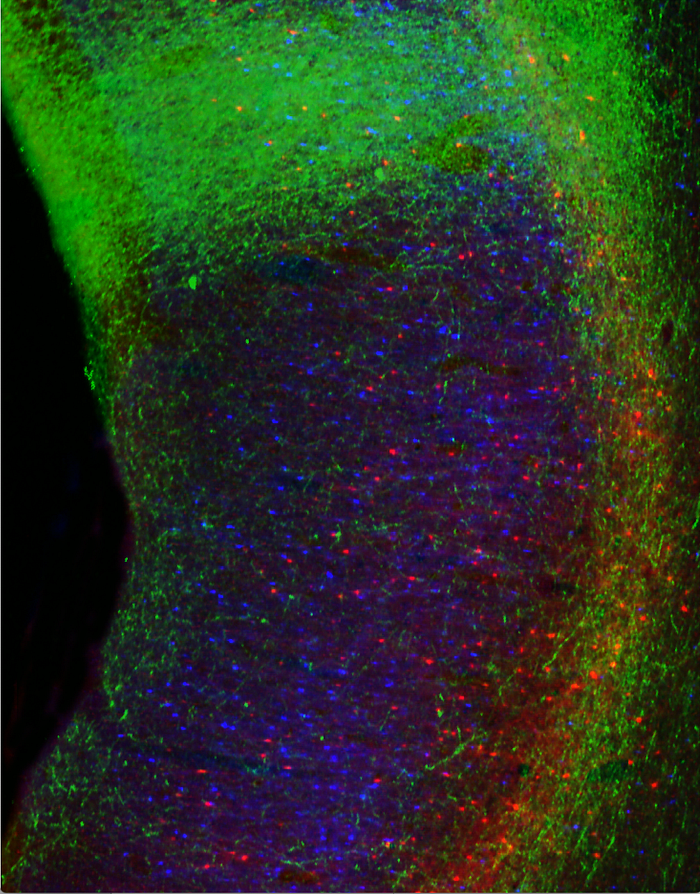

The researchers identified area 32 using neural tracers to visualize the connections between cognitive (DLPFC) and emotional (area 25) brain regions in rhesus monkeys. Their discovery helps us better understand what makes certain people more susceptible to depression — and can inform different treatment approaches.

So, what do these critical interactions between brain regions actually look like? The researchers take us into their lab for an inside-look: